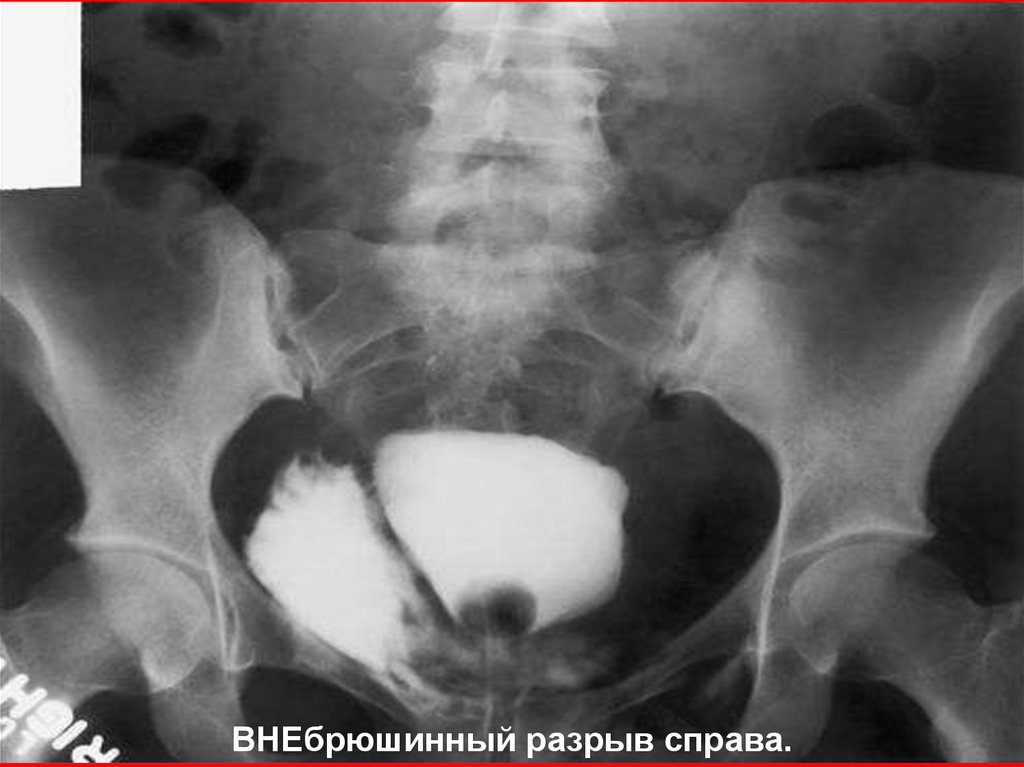

ВНЕбрюшинный разрыв справа.

ВНЕбрюшинный разрыв справа и костный отломок.